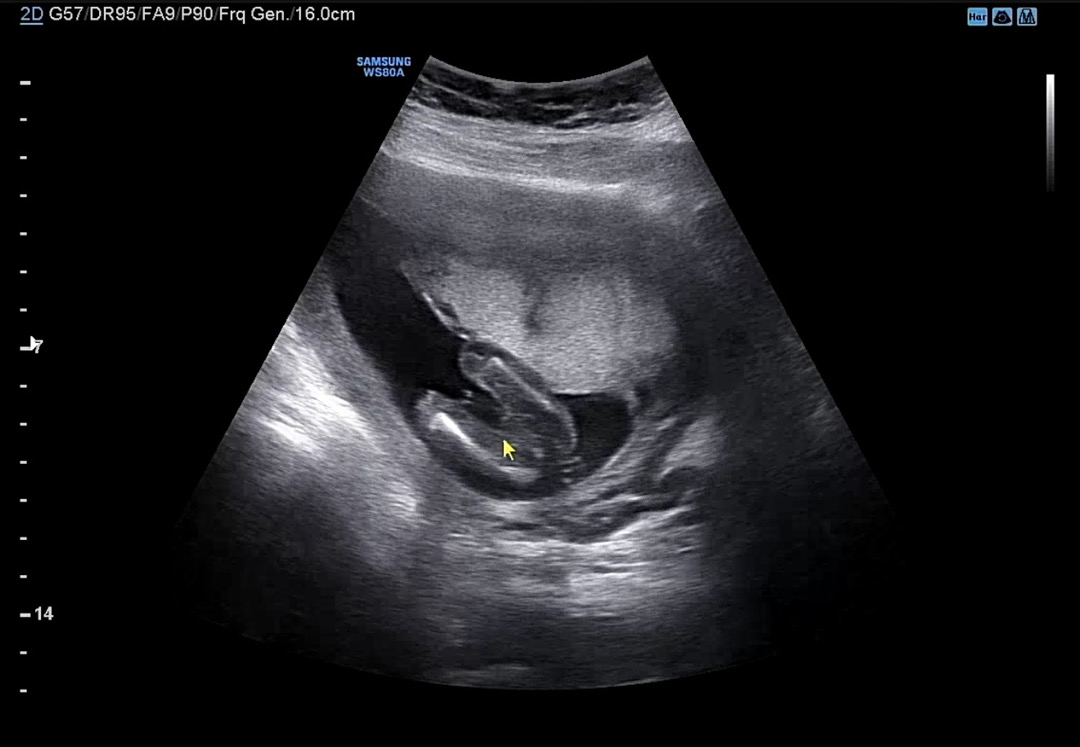

성별 .,, 도와주세요 ,,,,

둘째여서 딸이길 기도 기도 왕 기도 중인데 ,,, 도와주세요 ,,, 뭘까ㅛ …